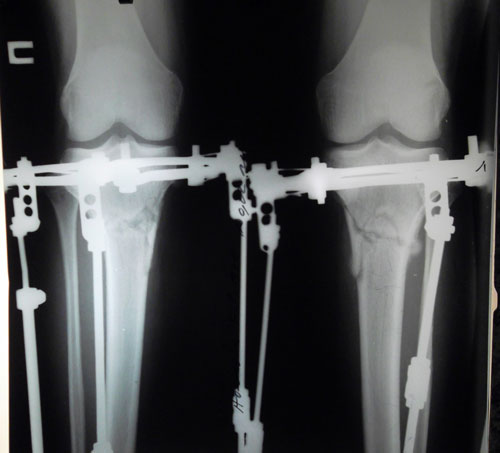

Отправляю фото ног. Посмотрите пж

Нагрузка на стопу стала равномерной, болей нет, теперь по сравнению с левой стопой ощущаю что правая стопа теперь болит, на внутреннею часть есть немного больше нагрузки. Незнаю с чем это связано, нога то вроде ровная.

Потом в правой ноге после исправления как приехала домой при ходьбе когда разгибаю колено появляется в колене какая то боль, как будто внутри что то разболталось, как будто спица внутри щелкает. Что делать? Так и ходить дальше?

Здравствуйте, П.! Все неприятные ощущения и боль - это временно, всё пройдёт. Ножки у Вас на славу - красивые! Продолжаем фиксацию! Re: Осенний марафон.